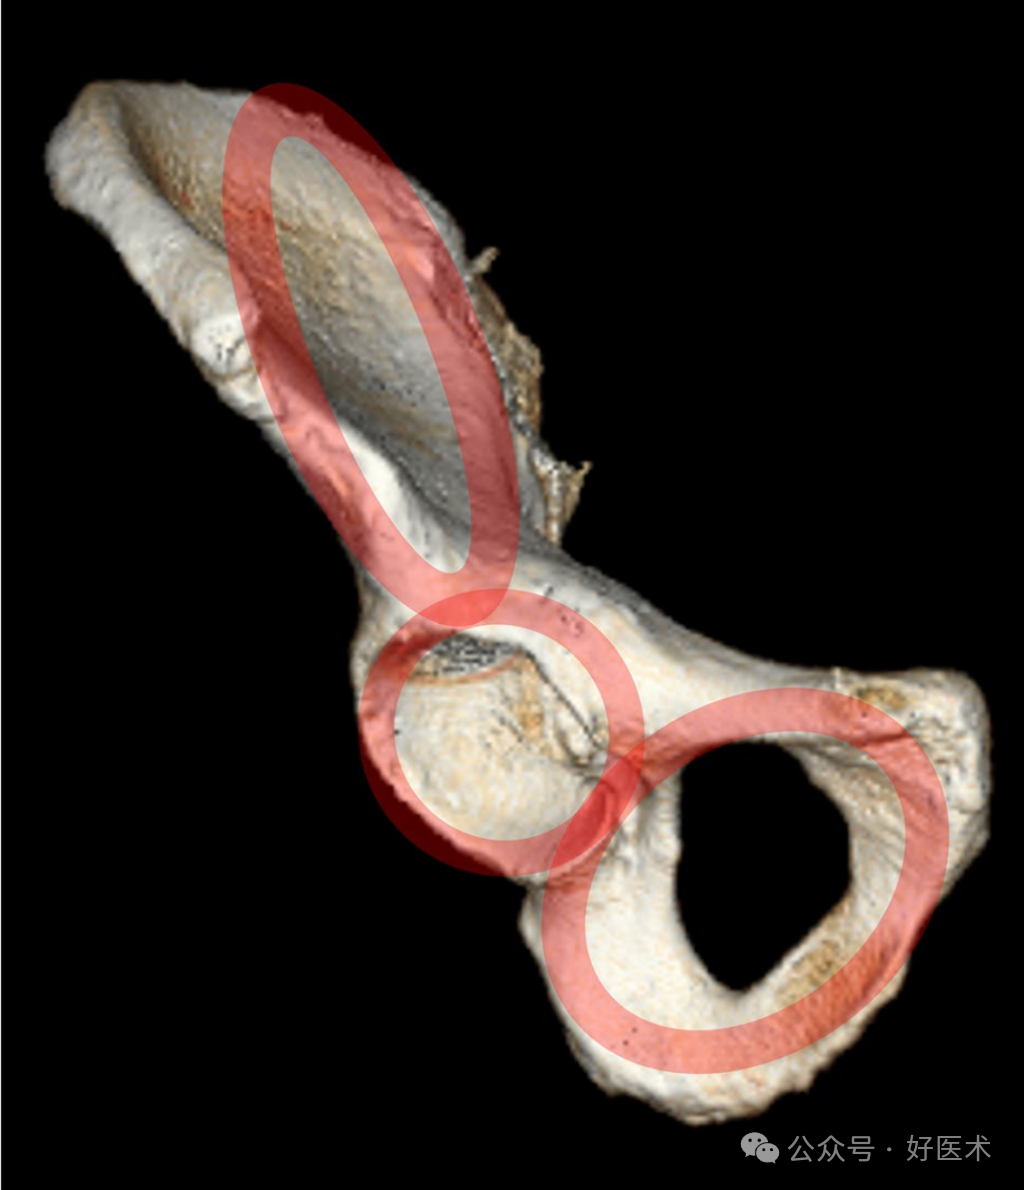

可以将半骨盆解释为由以下部分组成的三环结构(图1):

• 髂环

• 髋臼环

• 闭孔

图1 半骨盆由3个环组成,这对于植入物的适当定位非常重要:髂环、髋臼环和闭孔环。

在每个环中,中心部位没有骨骼或仅有少量骨骼。虽然闭孔环已经是一个真正的环,但髋臼和髂窝环结构仍然有一些小的中心骨骼,其**厚度为2—3毫米(图2)。在中国人中,髋臼环有时已经显示出真正的环状结构。

图2 中央髂骨(左侧两图)出现极端中央变薄情况的解剖结构。髋臼的中央、内侧部分(右侧两图)显示四边形板变薄。

因此,这些环状结构的外围适合在骨盆环和髋臼骨折手术中充分定位植入物(图1)。